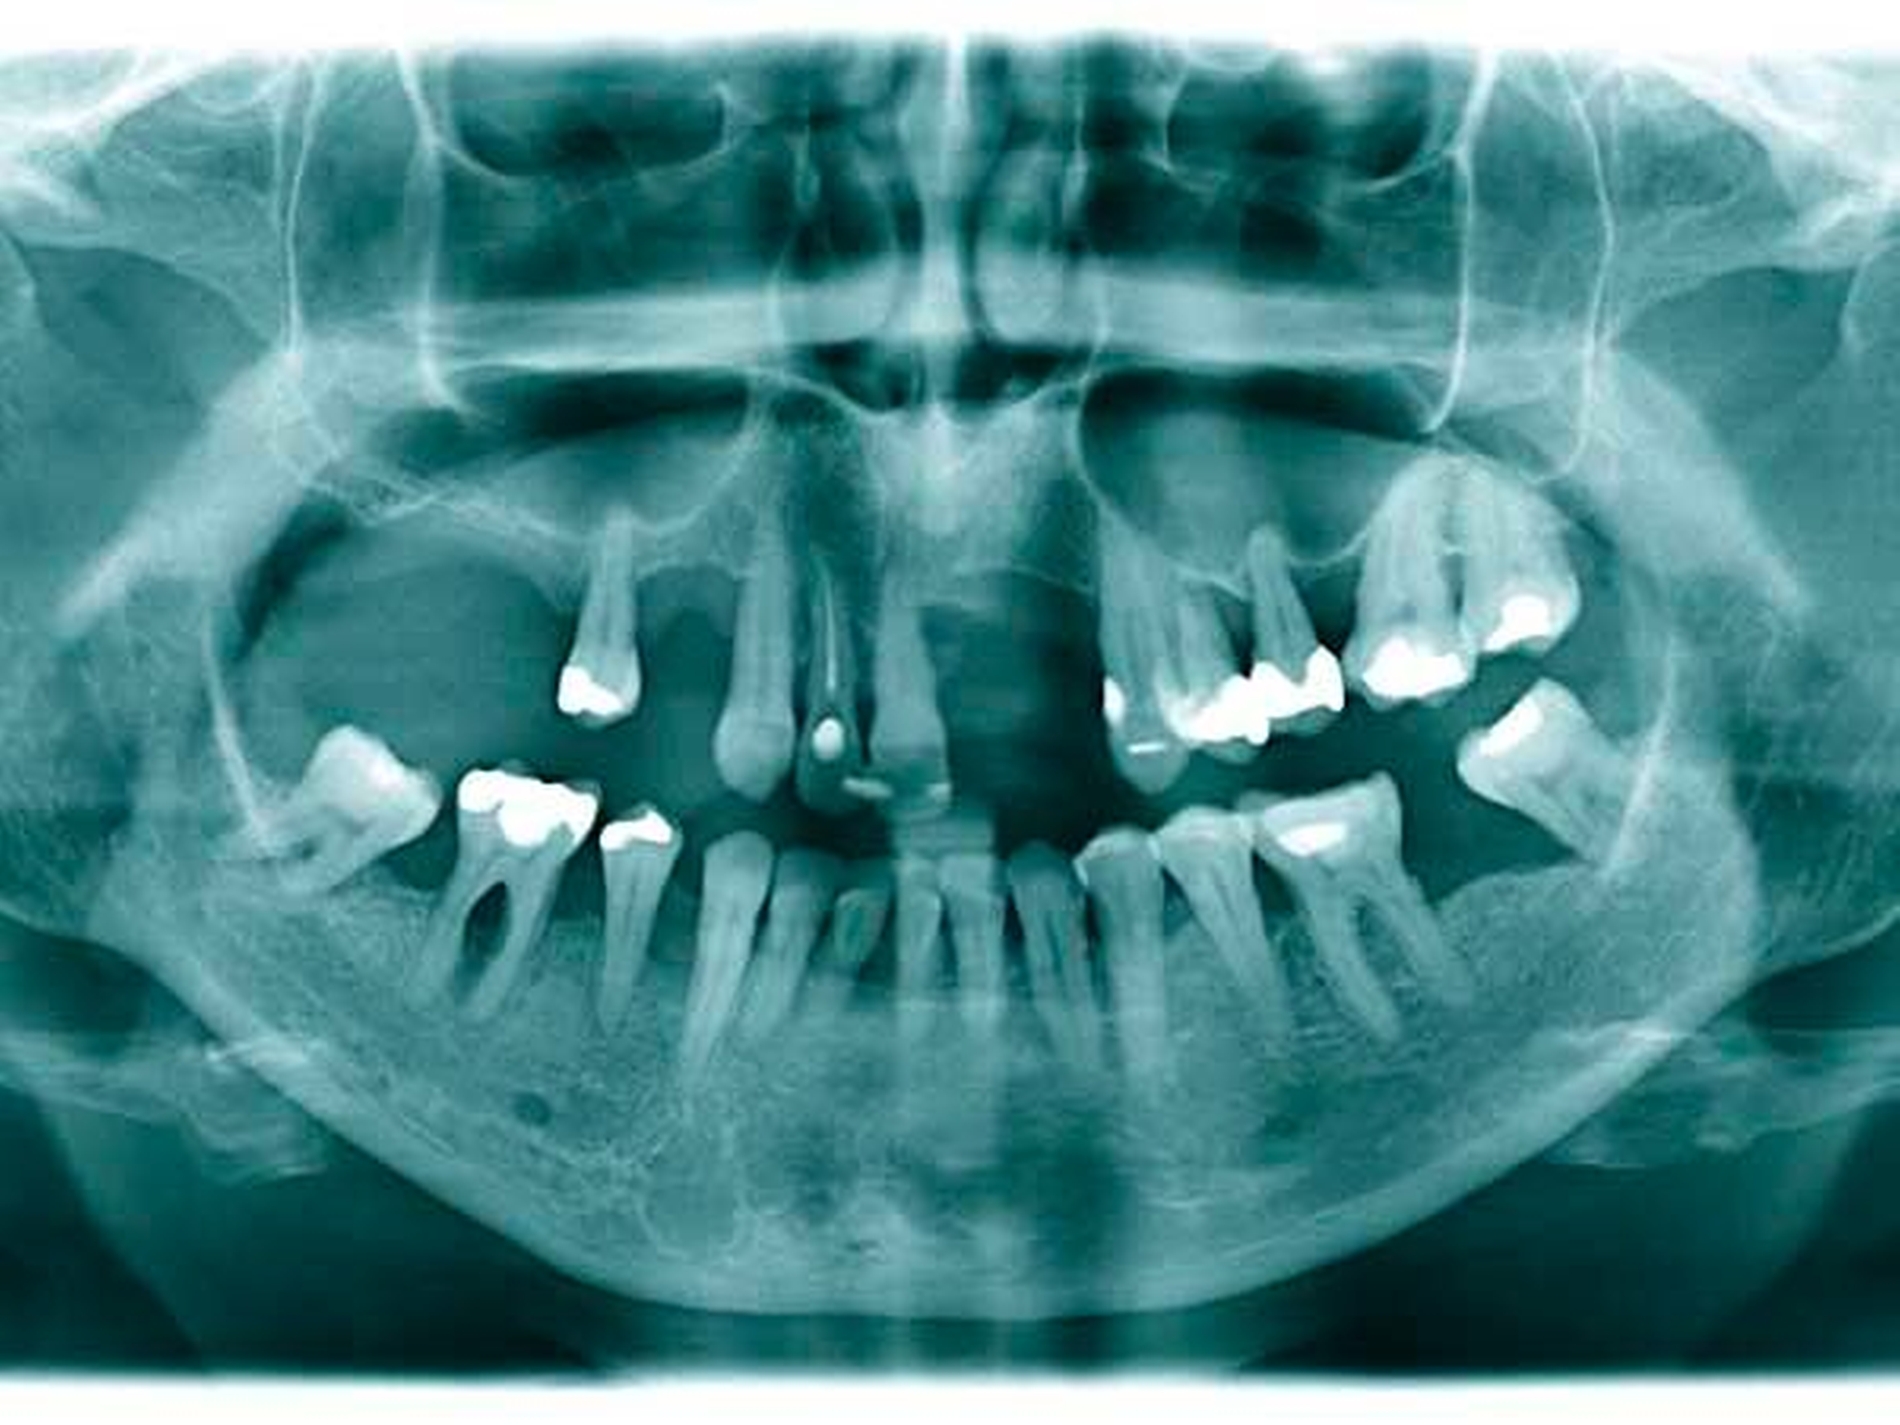

Das Orthopantomogramm (Abbildung 1) zeigt die desolate Gebisssituation einer 31-jährigen Patientin mit ansonsten unauffälliger Anamnese. Die Patientin wurde nach Abschluss der Extraktionstherapie zur prothetischen Beratung und Weiterbehandlung an unsere Poliklinik überwiesen.

Das Orthopantomogramm (Abbildung 7) zeigt die Gebisssituation eines 89-jährigen Patienten mit kardiovaskulärer Anamnese (Herzinfarkt, Stent-Implantate) und deutlich reduziertem, fast hinfälligem Allgemeinzustand. Der Patient erhält 14(!) verschiedene Medikationen. Der überweisenden Kollegin erschien die Behandlung in der Praxis zu riskant. Nach Abschluss der Extraktionstherapie stellte sich der Patient zur prothetischen Beratung und Weiterversorgung an unserer Poliklinik vor. Im Oberkiefer wurde ein totaler Zahnersatz geplant. Im Unterkiefer verblieb ein karies- und füllungsfreies Restgebiss von 33 nach 42 (Abbildung 8). Aus gesundheitlichen Gründen schied eine Präparation der karies- und füllungsfreien Zähne für die Aufnahme von Doppelkronen oder metallkeramischen Kronen mit oralen Fräsungen aus.

Das Orthopantomogramm (Abbildung 17) zeigt die Gebisssituation einer 49-jährigen Patientin nach Abschluss einer parodontalen Vorbehandlung. Die sehr gepflegte Patientin betreibt eine intensive Mundhygiene, legt hohen Wert auf ihre äußere Erscheinung. Ihre finanzielle Limitation lässt aber keine implantatprothetische oder aufwendige kombiniert festsitzend-herausnehmbare Versorgung zu. Da die Patientin eine hohe Lachlinie hat und eine Demaskierung durch sichtbare Gussklammern im Bereich der Frontzähne fürchtete (Abbildung 18), verweigerte sie konventionellen gussklammerverankerten Zahnersatz und trug entgegen ausdrücklichem zahnärztlichem Rat dauerhaft eine rein schleimhautgelagerte Teilprothese. Die Patientin wurde mit der Bitte um Beratung und Behandlungsübernahme an unsere Einrichtung überwiesen.